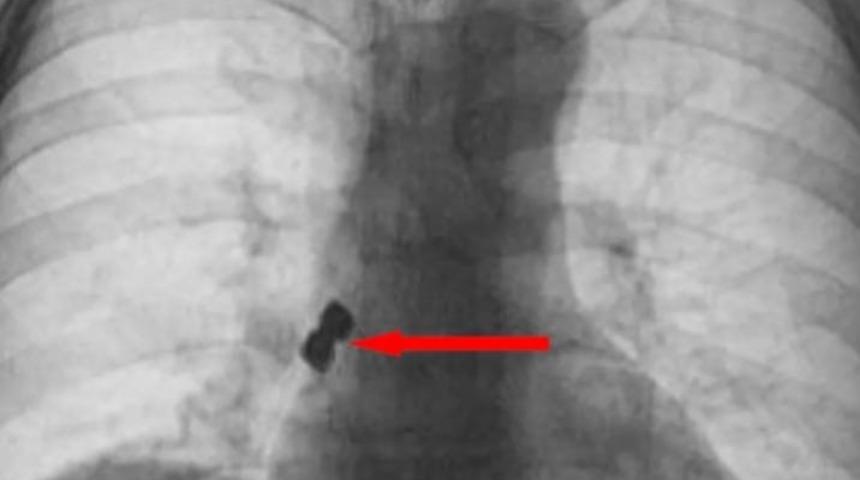

Yuttuğu dişler akciğerine kaçarak sağ nefes borusunu tıkayan 56 yaşındaki kadın ölümden döndü.

Olay Emirdağ ilçesinde meydana geldi. İddiaya göre, Belçika’nın Brüksel kentinde yaşayan 56 yaşındaki D.K., isimli gurbetçi vatandaş implant diş tedavisi için Emirdağ’daki bir kliniğe gitti. Operasyon esnasında birbirine yapışık halde olan 2 adet implant bir anda hastanın dişinden düştü. İmplantlar ardından hasta yutkununca akciğerlere kaçıp sağ nefes borusunu tıkadı. Nefes almakta zorlanan D.K., ardından Emirdağ Devlet Hastanesi’ne kaldırıldı. Burada yapılan müdahalenin ardından D.K., Afyonkarahisar kent merkezindeki bir hastaneye sevk edildi. Burada D.K.’nın akciğerine kaçan implantlar cerrahi operasyona gerek kalmadan, bronkoskopi yöntemi adı verilen tıbbi müdahale ile çıkarıldı. İmplant yüzünden ölüm tehlikesi atlatan D.K., birkaç gün hastanede kaldıktan sonra taburcu edildi.